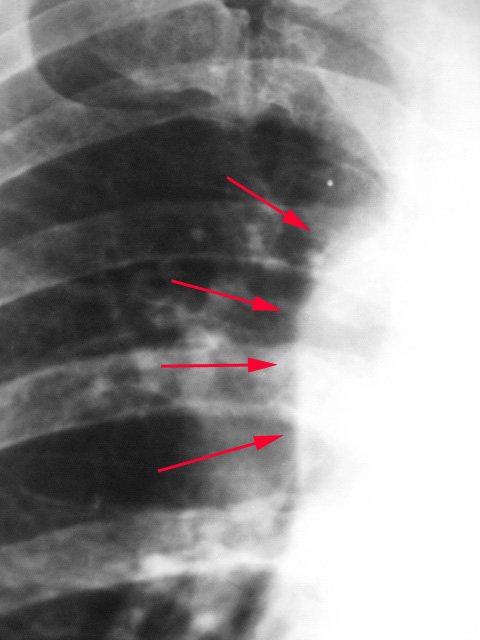

标题: X4751:M56Y,胸片会诊

男,56岁,体检。

横突。片效果差。

位置轻度右旋;

接上面内容,考虑升主动脉迂曲。

考虑升主动脉投影所致。

资料不全,第一映像是升主动脉

我认为是腔静脉迂曲形成的影像吧。

首先考虑迂曲的主动脉,其次考虑纵隔占位,加个侧位看看